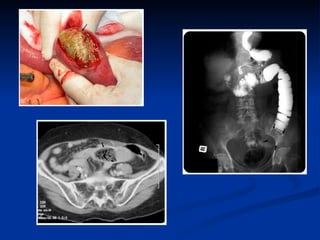

Large gallstones --  cholecystoenteric fistula – gallstone ileus Bezoars (children, mentally retarded, toothless, after gastrectomy) Congenital lesions (atresia, stenosis, duplication) Neoplasms of small bowel – peritoneal carcinosis Inflammation (Chron’s disease- diverticulitis- BK- endometriois) Fecal impaction (bedridden old patient) Meconium Foreign bodies Iatrogenic strictures (intest. Anastomosis o RT) Intestinal   mechanical   obstruction E tiology

Intestinal obstruction Is sensitive for diagnosing complete obstruction of the small bowel and determining the localization and cause of obstruction CT scan

Intestinal obstruction Issensitive for diagnosing complete obstruction of the small bowel and determining the localization and cause of obstruction CT scan